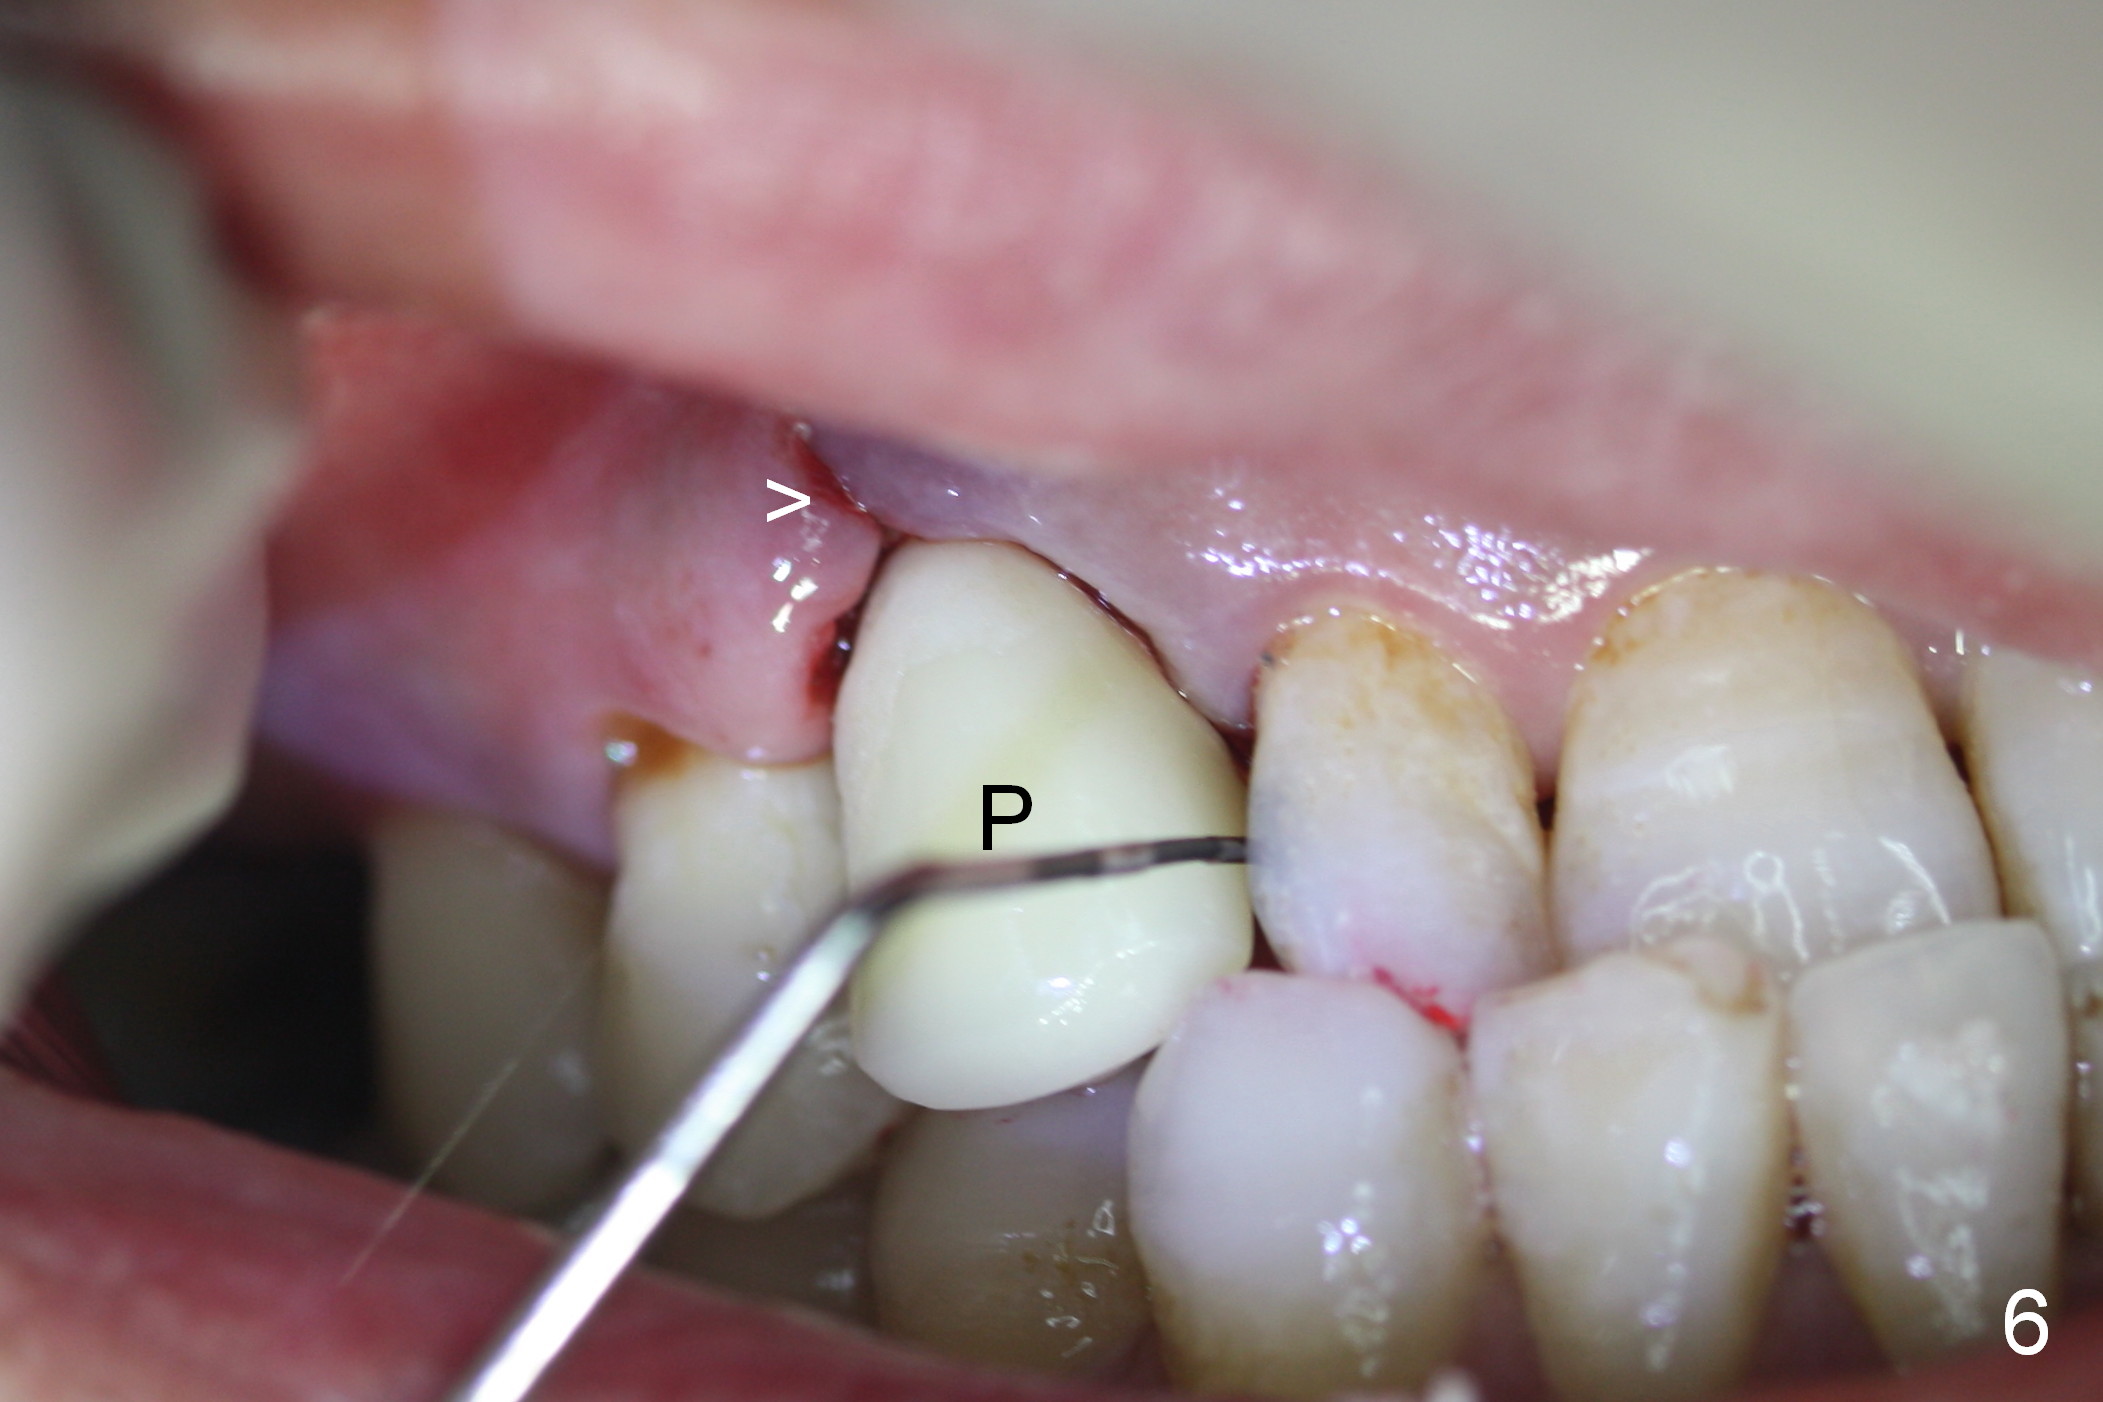

After 5x20 mm implant is placed, the distal gap is filled with bone graft (Fig.5 *). An abutment is placed (A) for fabrication of an immediate provisional (Fig.6 P). The latter hold the labial gingiva bulging (Fig.6 >). When the provisional is removed for bone grafting, the labial gingiva collapses (Fig.7 arrowheads). In fact a piece of cone-shaped Osteotape (Impladent) is placed palatal to the labial gingiva/thin labial plate and a small amount of graft is placed in the deepest area of the socket (labial to the osteotomy) prior to placement of the implant. More graft is placed in the peri-implant gap, particularly labially to keep the labial gingiva convex (Fig.8 arrowheads). The lacerated gingiva is to be approximated with perio glue (Fig.9 <). Collagen dressing is placed over the exposed graft before cementation of the provisional. Perio dressing is applied for further protection and seal.